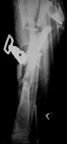

Tibia Fx ForumCase 1

I would appreciate treatment suggestions.My patient is a 30 year old with a very comminuted tibia fracture 6 weeks ago.It was grade 3B open. Initial treatment included irrigation, debridementClick images to enlarge.

and a hybrid external fixator including femur, tibia and foot. Screwswere placed in the plateau and plafond and a free flap plus STSG. Theskin is ok but atrophic. The femoral pins were removed and knee motionstarted at 6 weeks. There is no sign of callus. There is one pin inthe one large fragment of the diaphysis. All the pieces are lined upreasonably well. The XF pins are ok. Suggestions? Thank you.